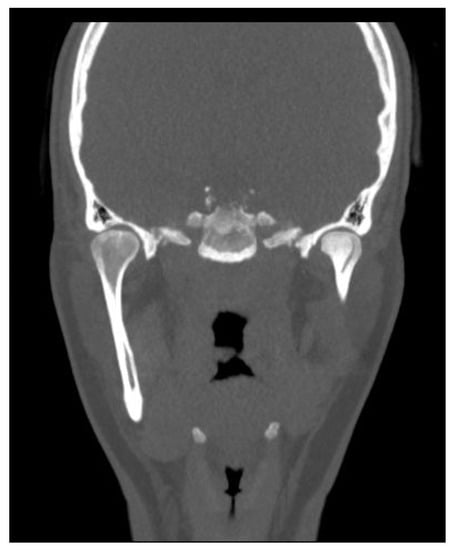

- A condylectomy with BSSO and Lefort I simultaneously was described by Wolford in 2002; however, some authors report operated TMJ joint instability, which might be related to the degree of excised bone and poor condyle stabilization with at least lateral pterygoid muscle reattachment or other, perhaps even related with IMF intramaxillary fixation devices to stabilize the occlusion [75] (Figure 9);